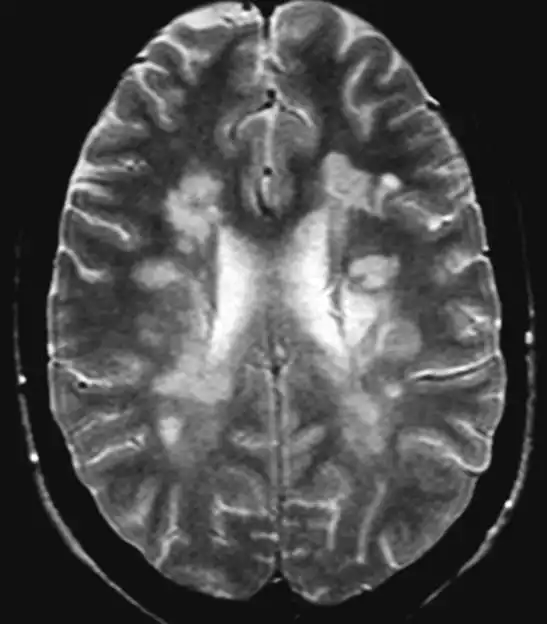

Los resultados del estudio indican que la lesión de la mielina, que es la capa protectora de las fibras nerviosas, puede comenzar aproximadamente siete años antes de que los pacientes noten cualquier síntoma. Este hallazgo es crucial, ya que sugiere que la enfermedad puede estar activa en el cuerpo durante un tiempo considerable antes de que se realice un diagnóstico. Además, la lesión axonal, que afecta directamente a las neuronas, se presenta alrededor de un año después de que se inicia el daño a la mielina.

Un aspecto interesante del estudio es el papel de los astrocitos, que son células clave en la protección del cerebro. Los investigadores encontraron que estos solo muestran cambios cuando la enfermedad ya es clínica, lo que indica que la EM puede actuar de manera silenciosa y asintomática durante años. Esto plantea un desafío significativo para los médicos y pacientes, ya que la detección temprana de la enfermedad es fundamental para implementar tratamientos que puedan prevenir daños irreversibles.